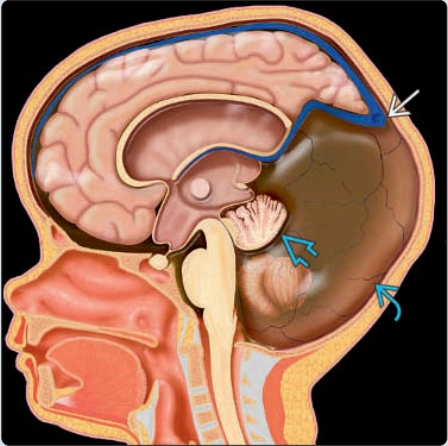

Dị dạng Chiari 2 thai nhi (Chiari 2 malformation)